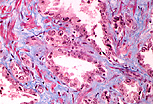

精囊为形态不规则、表面凹凸不平的盘曲管状器官,由黏膜层、肌层和外膜层构成。

黏膜具有细长的初级皱襞,初级皱襞上又布满常相互吻合的次级和三级皱襞,

形成呈蕾丝状、迷宫样的腔隙。

精囊的肌层较薄且排列不规则,分为内层环行肌和外层纵行肌。